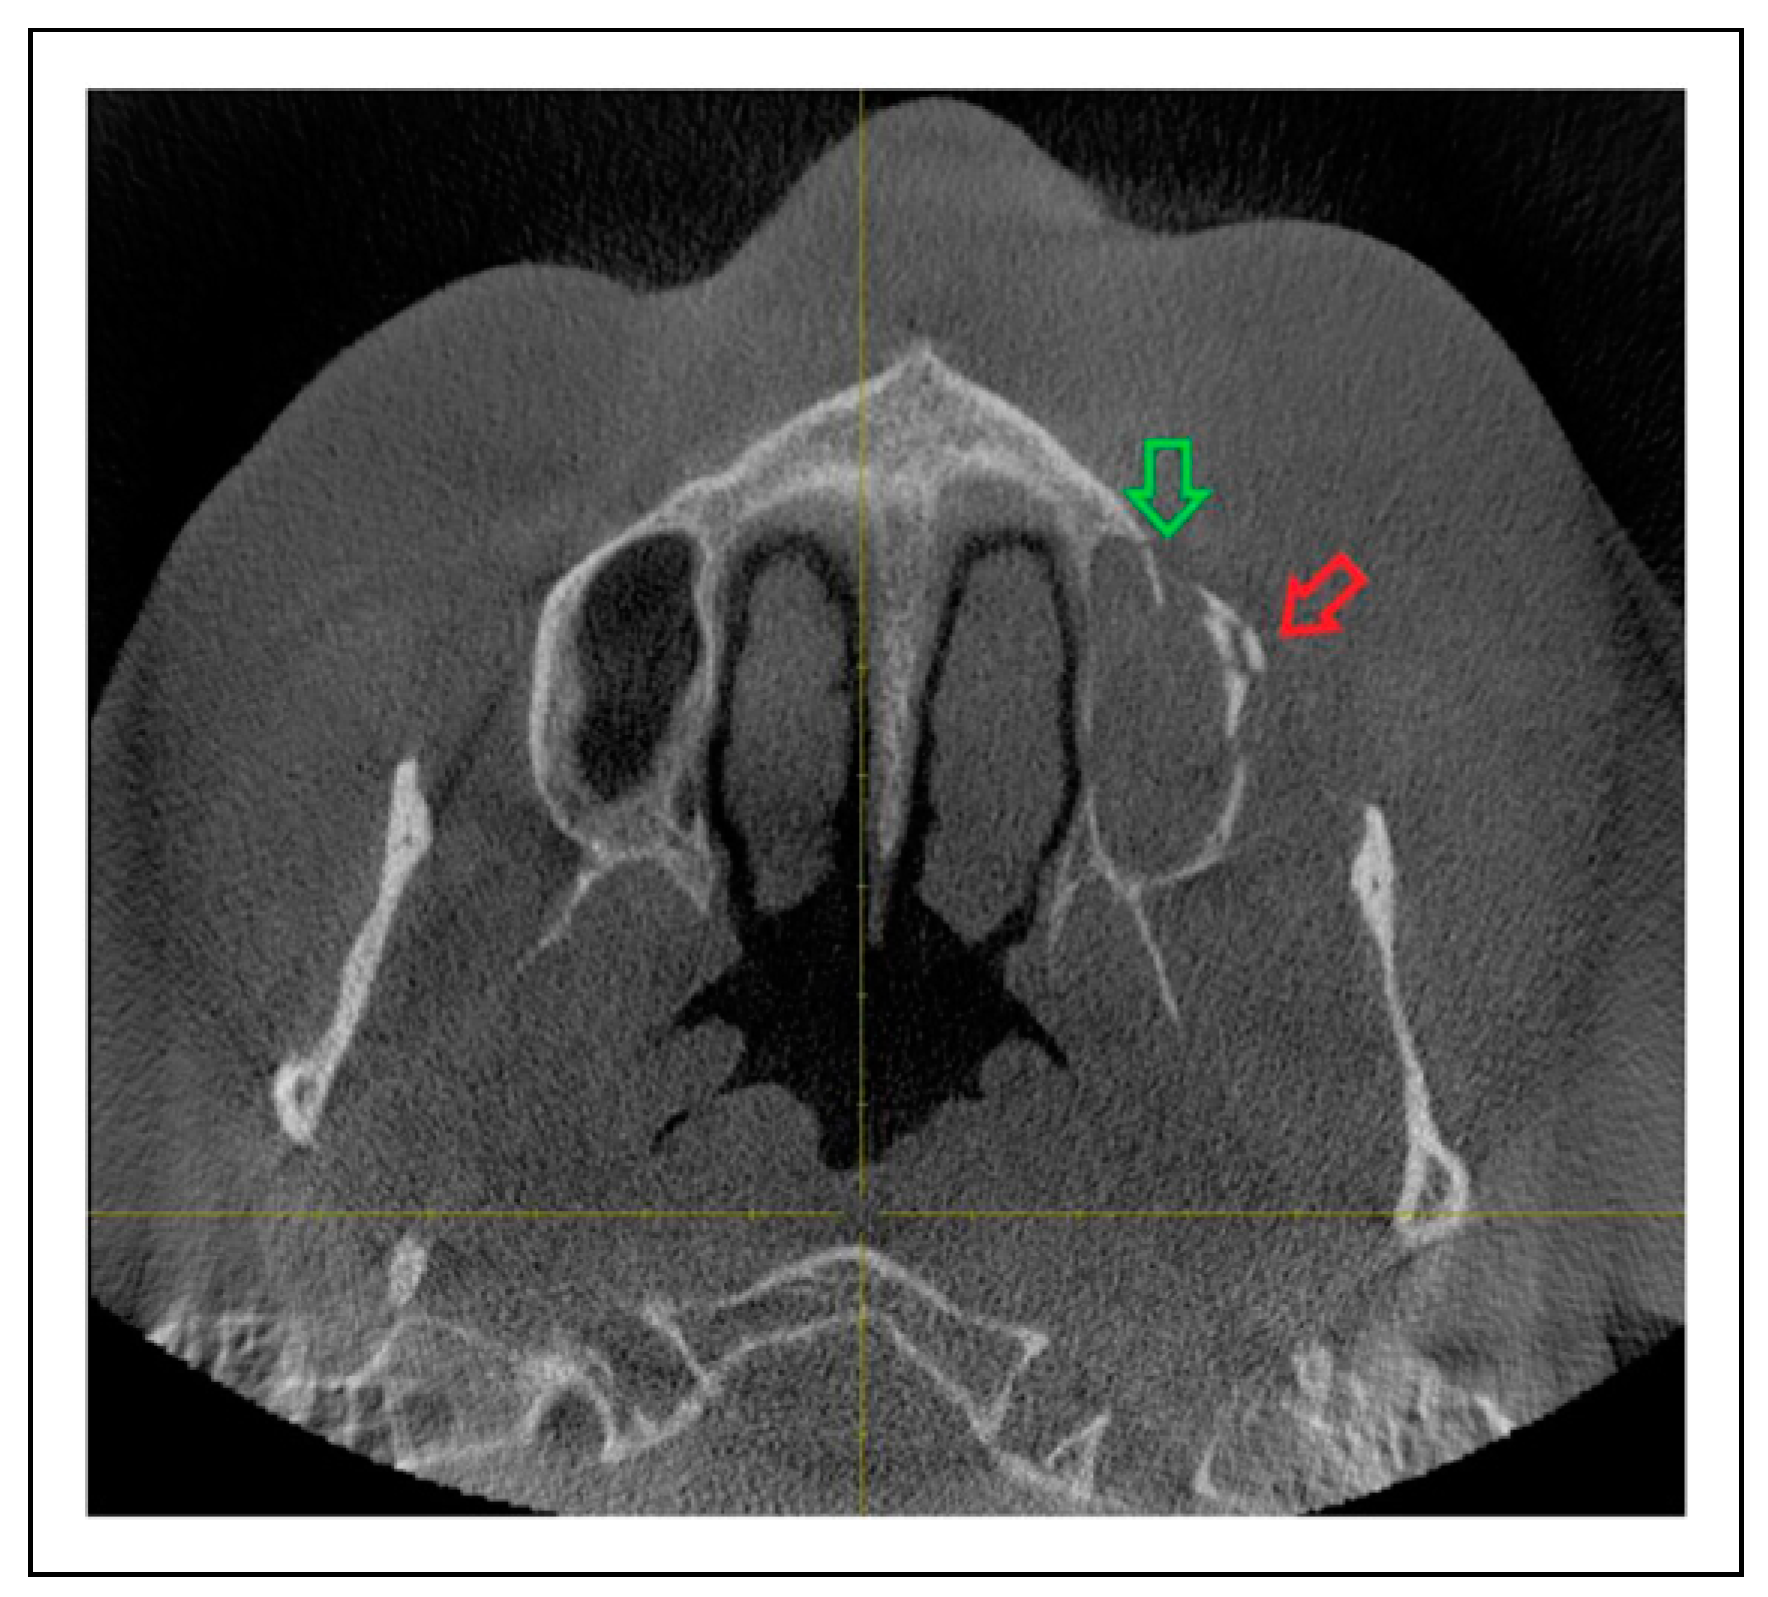

Patterns of ZMO Fractures Regarding the Anatomic Sutures of the Zygoma

- Zygomaticosphenoidal suture (ZS)—the anterolateral orbital floor

Fracture Prevalence of Maxillary Sinus Wall and Paranasal Buttress as Concomitance to the ZMO